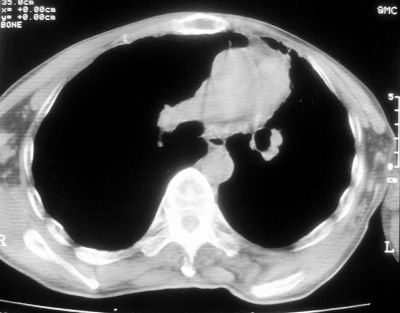

标题: CT11864:男,47岁,反复咳嗽、咯痰、咯血3年,请分析. [打印本页]

患者,男,47岁,反复咳嗽、咯痰、咯血3年,再发5天。痰培养未找到真菌、抗酸杆菌、癌细胞。

左肺上叶体积明显缩小,其内见多发透光区,纵隔向左侧移位,左肺下叶多发班片状病灶,边界模糊,1左肺上叶先天肺发育不全,2左肺下叶肺炎,

左肺上叶结核伴肺纤维化,纵隔移位,左肺下叶感染性病变,建议抗炎抗结核后复查,双肺气肿.

以下是引用xulianj在2008-2-25 21:01:00的发言:[br]左肺上叶结核伴肺纤维化有霉菌球形成,纵隔移位,左肺下叶感染性病变,建议抗炎抗结核后复查,双肺气肿.

考虑:左肺慢纤伴霉菌球形成、双肺全小叶型肺气肿。

1)考虑为:左肺上叶肺结核(空洞形成),伴左下肺感染;不排除霉菌感染可能。2)肺气肿。

左肺上叶结核伴肺纤维化空洞形成并左肺下叶感染,纵隔牵拉移位,建议作进一步检查排除左侧肺霉菌感染可能。